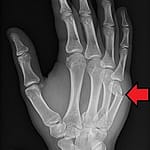

Hand Fracture Treatment and Care

Published on by The Hand & Plastic Surgery Center of KatyHand and Plastics Katy, led by Dr. Das, offers advanced reconstructive hand and wrist surgeries using microvascular and tendon repair innovations, personalized treatment, and compassionate, expert care. Continue reading

Restoring Function and Confidence after Hand and Wrist fractures

Published on by The Hand & Plastic Surgery Center of Katy

Hand and Plastics Katy offers personalized reconstructive hand and wrist surgery to restore function, boost confidence, and improve quality of life with expert care in Katy, Texas. Continue reading